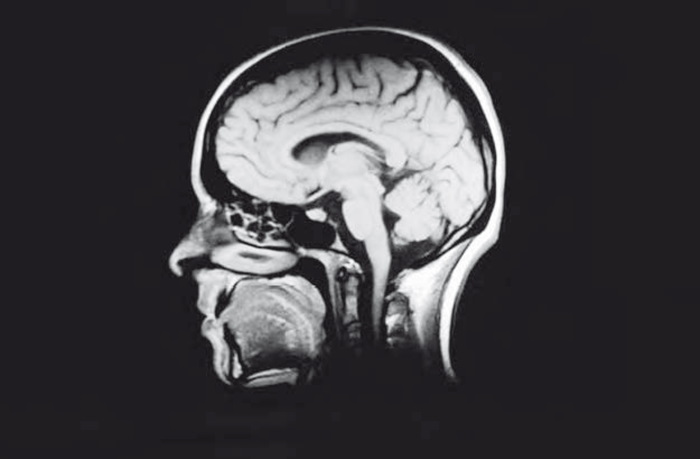

Все существующие научные объяснения ОСО изложены в Главе 6. Убедительная теория, объясняющая все многообразие аспектов ОСО, должна принимать во внимание как различные обстоятельства, при которых может происходить ОСО, так и характерные элементы, его составляющие. В Главе 7 я уделяю основное внимание проведенному в Нидерландах исследованию ОСО у 344 участников, переживших остановку сердца, а также сравнению результатов и выводов этого исследования с другими, сравнимыми с ним по масштабам и проведенными в США и Великобритании [14]. Во всех четырех приведенных проспективных исследованиях элементы ОСО отмечались в период остановки сердца, то есть при полной потере притока крови к мозгу. Как такое возможно? В восьмой главе подробно рассказывается о том, что происходит в мозге при острой нехватке кислорода, вызванной отсутствием пульса и артериального давления. Дополняя эти сведения, Глава 9 уделяет особое внимание нормальной работе мозга и ограниченности научных представлений, имеющихся в настоящее время в нашем распоряжении и относящихся к взаимосвязи между мозгом и сознанием.

© Сапцина У.В., перевод на русский язык, 2021